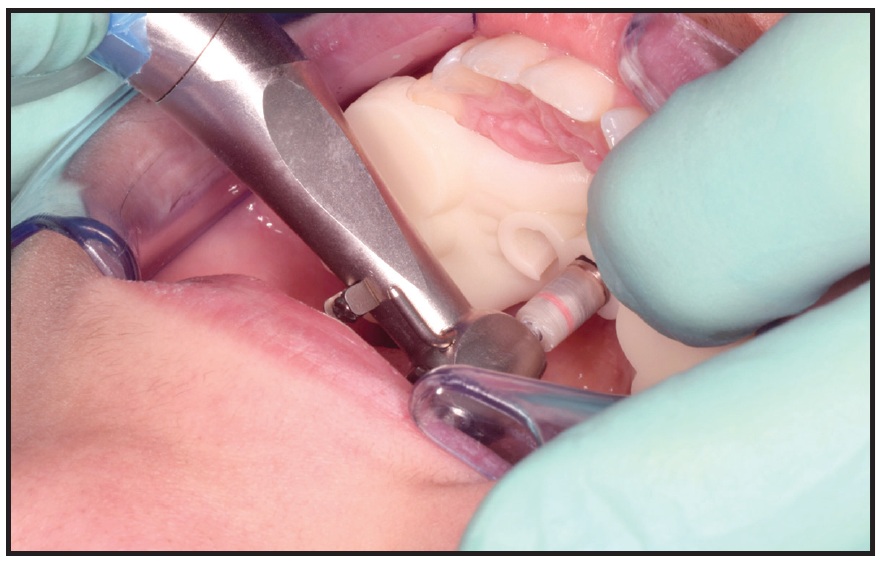

After local anesthesia (2% lidocaine) was administered in the surgical sites, the surgical guide was fitted to the occlusal surfaces of the posterior teeth. Two OrthoEasy Pal** miniscrews were inserted into the adapted pickup driver and mounted on a contra-angle handpiece at a low speed of 40rpm (Fig. 8). The cylindrical guide tubes were designed according to the dimensions of the pickup driver to ensure that the screws were inserted at the correct angle and the planned depth (Fig. 9).

Fig. 8 Insertion of OrthoEasy Pal** miniscrew using surgical guide.